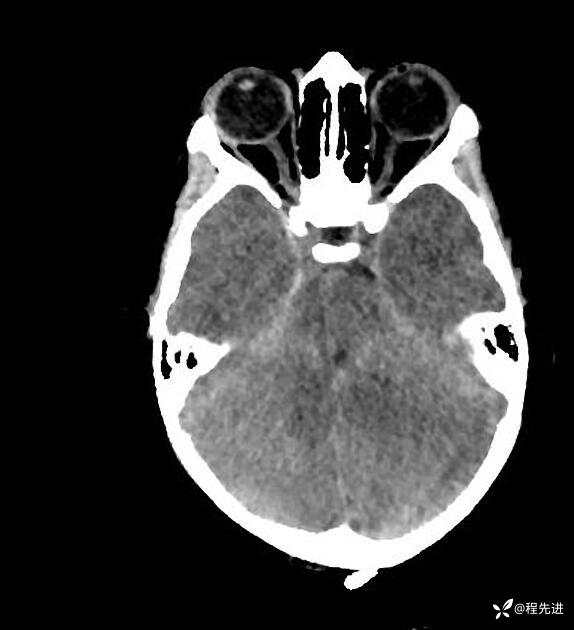

患者性别:男

患者年龄:5岁

简要病史:超速车祸外伤半小时

急诊CT平扫: